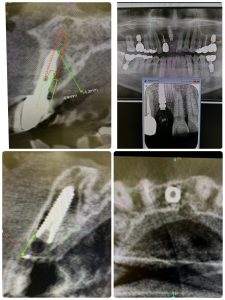

次は、4年ぶり来院😭、デンサーリフト定期検診

異物人工骨は無し!

採血より得られた、濃縮血漿板のみ入れる

あとは、自家骨の圧縮、飛散のみ

グラフトレス サイナスフロアー エレベーション!

パワーtype力の方であり、無養生だが非常に安定🤪

骨がモリモリ、ワイドインプラント径6.5ミリは非常に良い、安定性👌